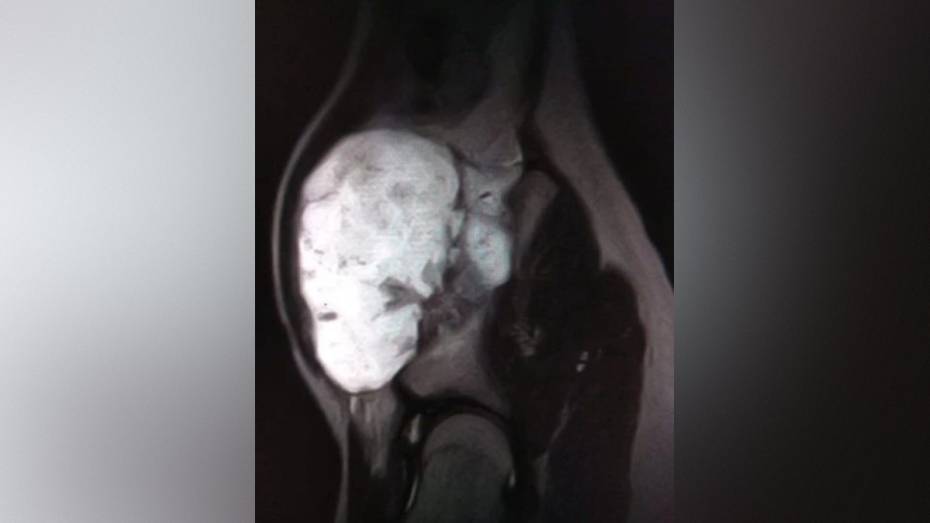

Врачи областной детской больницы №2 удалили 13-летнему пациенту большой нарост на кости. Парень наблюдался в больнице с редким диагнозом – экзостозная хондродисплазия. При таком заболевании кости образуется костно-хрящевое разрастание. У пациента появилось образование 12 на 9 на 7 см. Нарост болел и причинял дискомфорт, кроме того, образование угрожало здоровью тазобедренного сустава. Об этом сообщили в пресс-службе министерства здравоохранения Воронежской области.

У пациента нарост появился на подвздошной кости – сложной анатомической области, требующей от хирурга особой точности. Бригаде под руководством заведующего отделением ортопедии ОДКБ №2 Александра Птицына предстояло не просто удалить нарост, но и сделать это максимально бережно, чтобы не повредить окружающие ткани, сосуды и зоны роста кости.